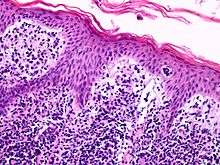

Lutzner cells were discovered by Marvin A. Lutzner, Lucien-Marie Pautrier, and Albert Sézary. These cells are also referred to as Pautrier’s abscess, Sézary’s cell, or Sézary-Lutzner cells. They are a form of T-lymphocytes that has been mutated[1] This atypical form of T-lymphocytes contains T-cell receptors on the surface and is found in both the dermis and epidermis layers of the skin. Since Lutzner cells are a mutated form of T-lymphocytes, they develop in bone marrow and are transported to the thymus is order to mature.[2] The production and maturation stages occur before the cell has developed a mutation. Lutzner cells can form cutaneous T-cell lymphoma, which is a form of skin cancer.[3]

Lymphocytes are white blood cells that form from a blood stem cell, hemocytoblast, in bone marrow and travel to other parts of the body, normally specific lymphoid tissues, to mature. After being produced, the stem cell differentiates into lymphoid stem cells. Then, T-lymphocytes further mature and differentiate into lymphoblasts when the hormone thymosin is secreted from the thymus. Finally, specialized immune cells, B cells and T cells, and nonspecialized immune cells, nature killer cells, are created from the lymphoblasts. This process is referred to as Leukopoiesis. Lutzner cells are an atypical form of T-cell lymphocytes and are normally CD4+.[2] Lutzner cells develop because of clonal gene rearrangements in the T-cell receptor or antibody. This rearrangement occurs early in the differentiation process and creates novel T-cell receptors that mimic the structure of normal antibodies but are not able to function properly. This mutated form contains an enfolded nuclear membrane and has a cerebriform shape, resembling the shape and folds of the brain.[4] Lutzner cells can be best seen through electron microscopy because it is able to show the 3-D structure of the cell.

The mutated cells are mature T-lymphocytes and contain CD4+ receptors on the membrane surface. There are two variants of this mutated cell, Lutzner cells and Sézary cells. Sometimes these names are interchangeable, but it has been determined through histology that they are morphologically different.

Lutzner cells

Lutzner cells are bigger than normal lymphocytes and contain extensive folding in their membrane. They are described at being cerebriform in shape, and can be diploid or tetraploid. It also contains a large nucleus with a minimum cytoplasm. Lutzner cells are more predominant in Mycosis Fungoides, but are also found in Sézary Syndrome.[6]